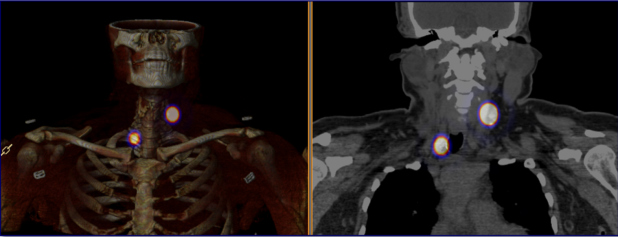

Las figs 2-5 ilustran casos de la serie analizada.

Resultados

Se analizaron 17 casos, 15 mujeres y 2 hombres, con edad promedio de 50,4 años (23-73 años). Se identificó carcinoma papilar clásico en 15 pacientes y papilar variante folicular en 2, con varias intervenciones previas por LLRCT (en promedio 2,3 intervenciones por paciente). La TGB pre quirúrgica promedio de 23,9 ng/ml (3-123 ng/ml), descendió posterior a la cirugía a un valor promedio de 4,6 ng/ml (aunque fue medida sólo en 12 casos). En la tabla 2 se resumen los resultados.

En cuanto a la efectividad quirúrgica, se extirpó el 100% de las lesiones radiomarcadas (17/17); de ellas, 16/17 (94,1%) fueron positivas para LLRCT. En el 47% (n=8) fueron recurrencias y en 53% (n=9) adenopatías secundarias.

Efectos del AMESPECT

- En 13/17 casos (76%), incrementó un 25% el tamaño detectado de las LLRCT respecto a la ecografía inicial (de 12,6 mm promedio a 16,8 mm.).

- Se reconocieron 22 nuevas lesiones (129% más) sospechosas de LLRCT en 11/17 pacientes (65%), en quienes modificó el plan quirúrgico; 82% de las nuevas lesiones fueron positivas para carcinoma tiroideo.